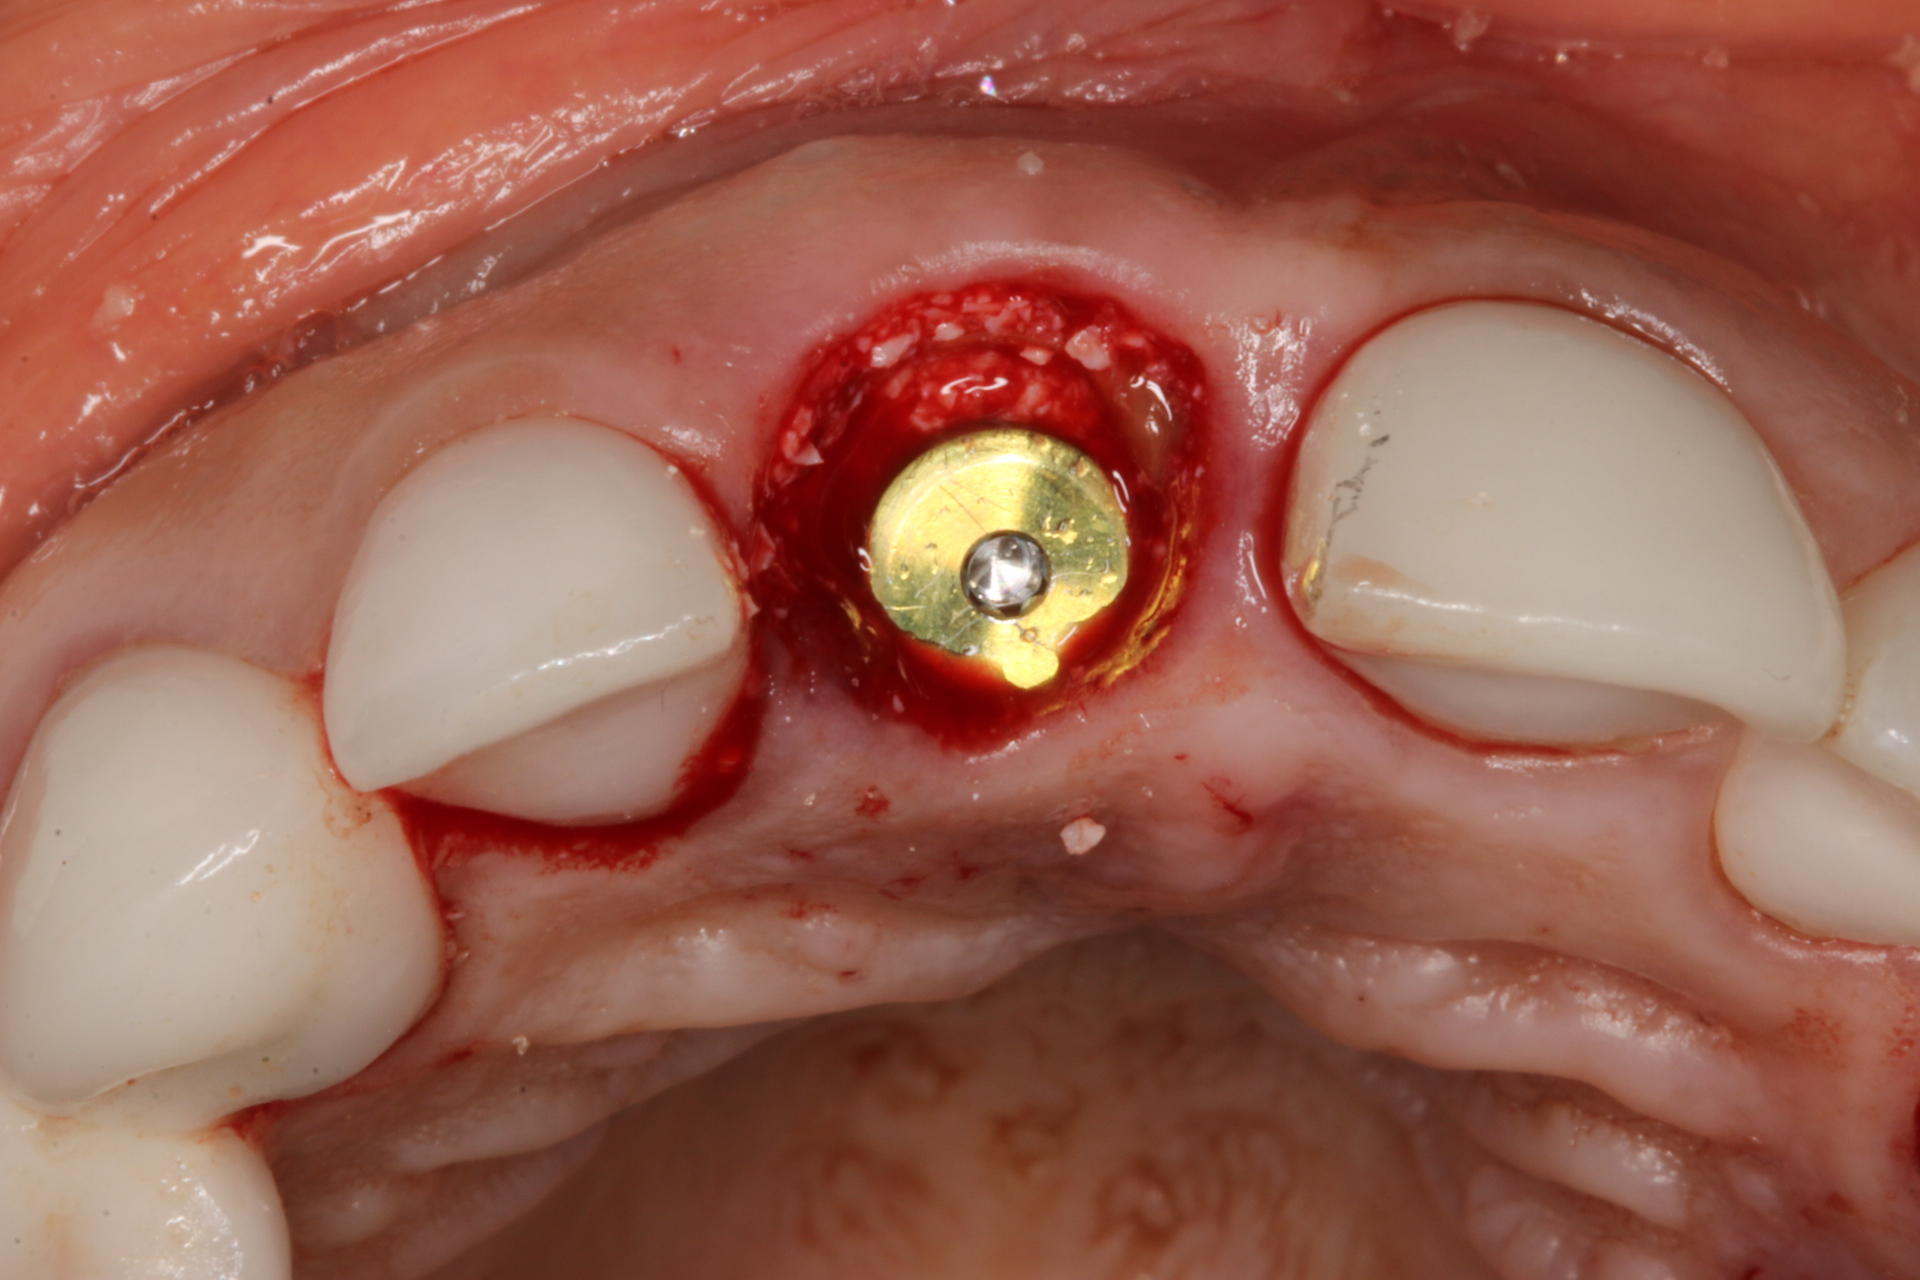

Dedicated to understanding and implementing the ridge augmentation blue print. All about socket grafting, bone, soft tissue, membranes, PRF, materials. We also included a hands-on exercise for soft tissue grafting and suturing.

• The wonderful socket shield technique - Do's and Don'ts

• Contour grafting around implants - the Keys to your success